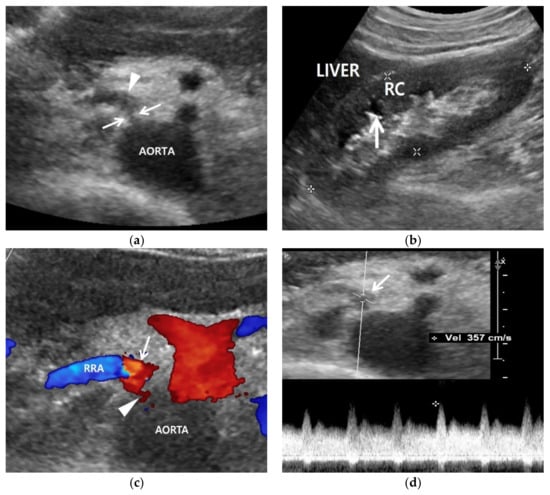

Figure 2.

Renal artery and renal US examinations of a 50-year-old man. (a) Gray-scale US axial image shows focal stenosis (arrows) in the proximal right renal artery (RRA) and poststenotic dilatation (arrowhead). His RAS was incidentally detected in the routine check-up because his clinical or laboratory findings were unclear. (b) Gray-scale US sagittal image that shows a small (9 cm) right kidney in which the cortex (RC) is more hyperechoic compared with the liver parenchyma. Arrows indicate clear cortico-medullary differentiation in the right kidney. (c) Color Doppler US shows a focal stenosis (arrowhead) in the proximal renal artery. Bright red and blue signals are seen in the poststenotic dilatation (arrow). (d) Spectral Doppler US shows a high PSV (357 cm/s) in the poststenotic dilatation (arrow). However, a low PSV (108 cm/s) was measured in the stenotic artery because the frequency shift from the RAS was not sufficient.

Gray-scale US can show indirect signs of RAS in the kidney (Table 3). The size of an RAS-involved kidney is smaller than the other uninvolved kidney [42] (Figure 2). The renal cortex becomes thinner than the medulla because the former is more susceptible to hypoxic damage than the latter. The hypoxic cortex becomes hyperechoic, so that the cortico-medullary differentiation of an involved kidney becomes clearer than that of the other uninvolved kidney (Figure 2).

5.2. Color Doppler US

Color Doppler US shows mainly blue or red signals in the normal renal artery. The brightness of these signals is increased in the renal artery (Table 4). The speed of blood flow increases as RAS becomes severe (Figure 3). These Doppler signals show mixed bright red and bright blue colors in the poststenotic dilatation because turbulence is created from the back-and-forth high-speed blood flows out of the stenosis by means of colliding with the lumen of renal artery (Figure 2 and Figure 3).